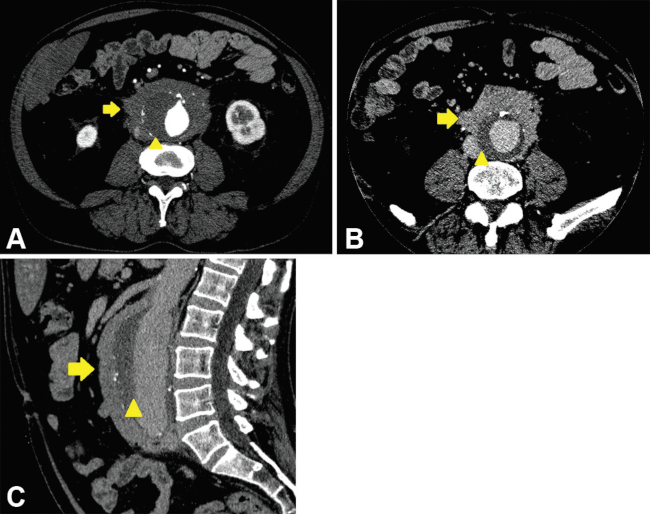

Aneurisma aórtico inflamatorio idiopático

Se distingue del aneurisma ateroesclerótico por presentarse con engrosamiento de la pared, acompañado por fibrosis densa que puede llegar a envolver estructuras adyacentes, tales como el duodeno, el uréter y la vena cava inferior. Ocurren en la porción infrarrenal de la aorta abdominal y en pacientes más jóvenes que los afectados por la causa aterosclerótica.2,16

Una característica distintiva del aneurisma inflamatorio idiopático es que el engrosamiento parietal afecta predominantemente la pared anterior del vaso (►Fig. 4.).1

El principal diagnóstico diferencial es la fibrosis retroperitoneal, en la que, además de reacción inflamatoria fibrótica, se observa dilatación de la aorta, y el aneurisma micótico, debido a la similitud clínica, imagenológica y laboratorio (elevación de la proteína C reactiva).2 En cuanto a las características imagenológicas, el aneurisma micótico suele ser sacular, irregular y pueden encontrarse burbujas aéreas circundantes, a diferencia del aneurisma inflamatorio que suele ser fusiforme (►Fig. 5).16